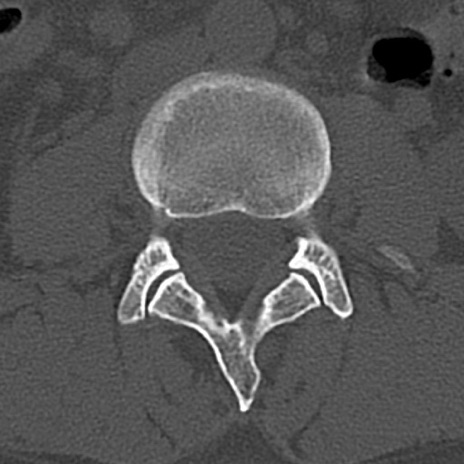

腰椎CT

横断像と矢状断像